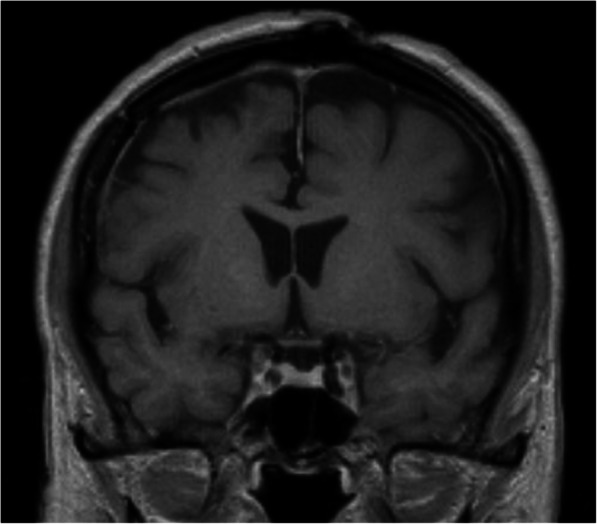

Fig. 5.

Postoperative MRI. T1 weighted image, coronal section. No residual or recurrent tumor mass